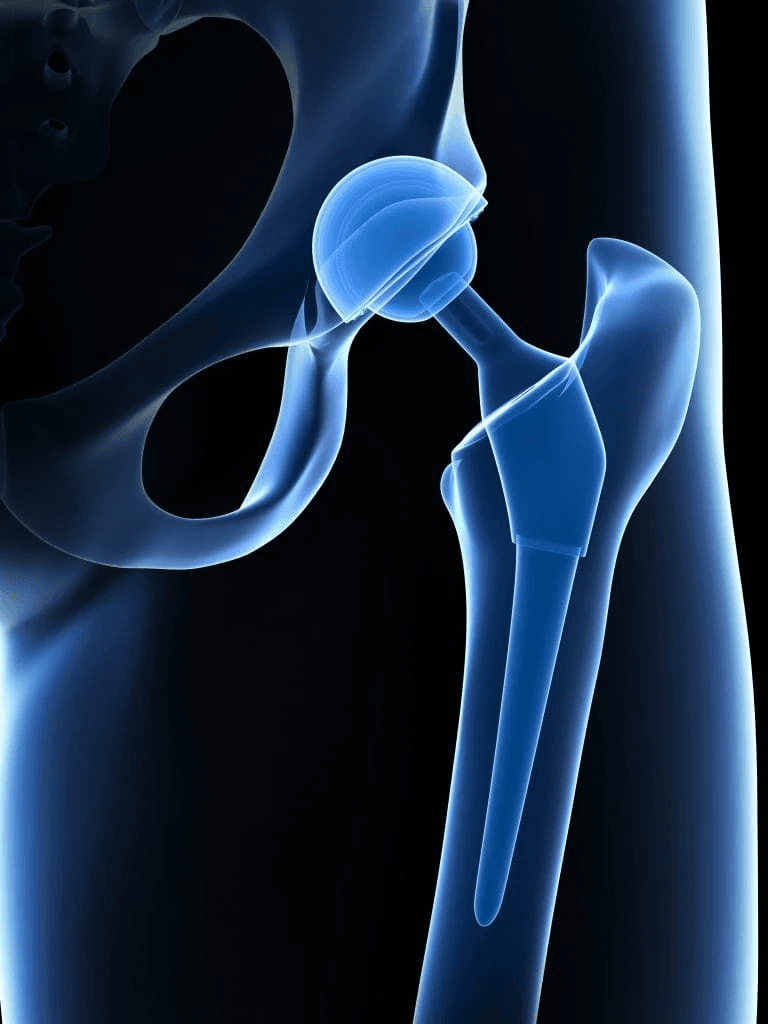

Dr. Ankur Singh is a highly experienced Senior Orthopedic Surgeon with over 15 years of expertise in Arthroscopy, Sports Medicine, Arthroplasty and Robotic Joint Replacement. He specializes in advanced knee, shoulder and hip surgeries, including primary, complex, and revision joint replacements, ligament reconstructions, cartilage restoration, osteotomy and joint preservation procedures.

Advanced 3D surgical mapping and robotic systems allow millimeter-level accuracy and optimized implant positioning.